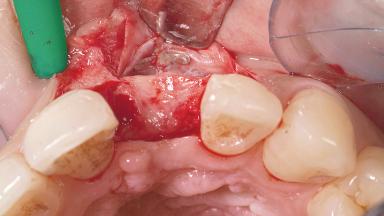

A 30-year-old female patient had lost tooth 21 and was referred to our clinic for consultation and treatment. Due to advanced apical infection, tooth 21 had been extracted two months earlier at another clinic and an acrylic-resin tooth had been bonded to the adjacent teeth. The patient desired implant treatment to avoid any damage to the adjacent natural teeth. While the patient had no history of any systemic disorder, she was a heavy smoker and exhibited medium to advanced periodontitis in the entire jaw. After the initial treatment to achieve a pocket probing depth of less than 4 mm and no bleeding on probing, a decrease in the height of the papillae mesial and distal to the extraction site and overall gingival recession were observed.

| Bone Augmentation | Horizontal|Staged |

| Augmentation Materials | Autogenous chips|Membrane |

| Soft Tissue Grafting | Simultaneous |